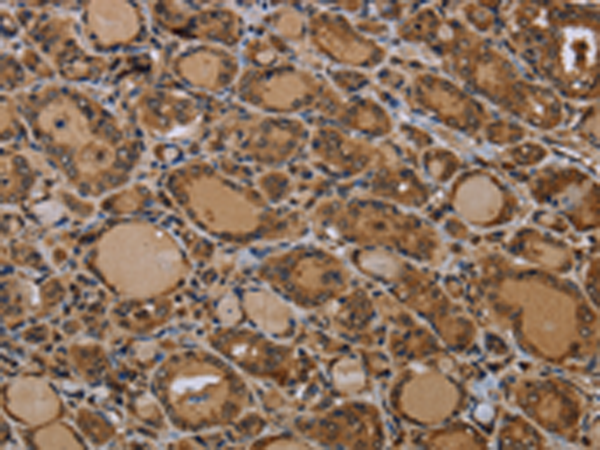

分类: 科研抗体货号: P11213别名: KPM应用: IHC反应种属: Human, Mouse